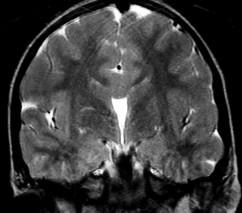

Alobar

Most severe, complete lack of “cleavage”, fused thalami.

Semilobar

“ in between” with separated occipital lobes

Lobar Mild, often only anterior frontal lobe fused, with separate thalami